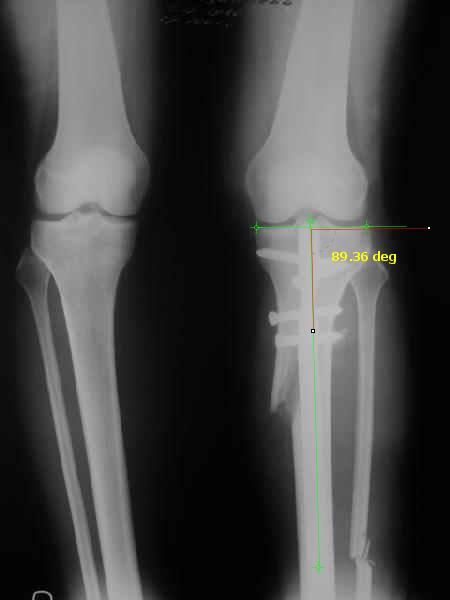

Отправитель: T. Derek V. Cooke 13 Сентябрь 2005, 23:51

|

Hello Alex:

Thanks for the clinical photo.

Your patient appears to have "Insquinting Knees"?

I am attaching a word doc with a 'print screen' of the program in use, showing the images being viewed and analysed

. On the right leg you can see some of the tools (from the tool bar above) applied to demonstrate a mild mech-axis varus of about 5 degrees.

On the left the bone landmarks used in the anlaysis are shown.

The data for the analysis are in the XLs sheet below, exported from the program automatically.

I have given a label of the abreviations and some normative values.

In essence she has a mild mech-axis varus of 7 degrees with some contribution from the femur (2) degrees and more from the tibia (6 degrees), none from the joint.

The analysis took about 6 mins.

Regards

Derek

TDVC> In essence she has a mild mech-axis varus of 7 degrees

TDVC> with some contribution from the femur (2) degrees and more from

TDVC> the tibia (6 degrees), none from the joint.

And what is conclusion? Should it be corrected, by what means, at what level, to what axis, with what lateral/medial translation?

Can the attached result be analyzed by the software?